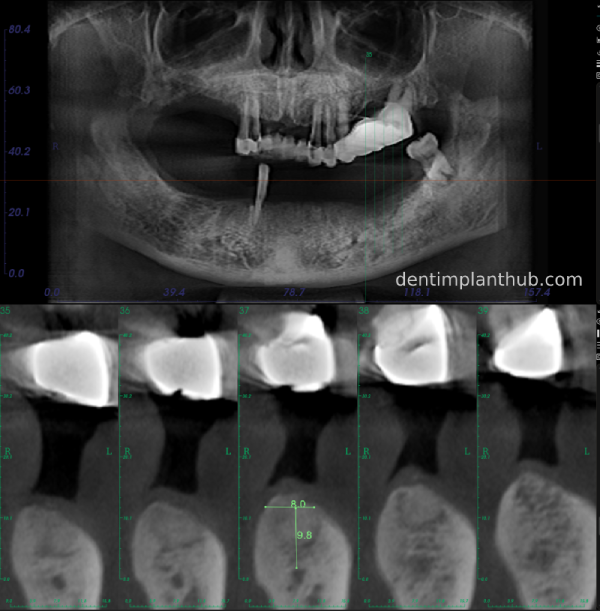

A review of the CBCT on 6/10/23 was more promising and a surgical plan was subsequently drawn up.

46

44

42

32

34

36

General schematic of the surgical programme

Detailed list of implant types and composite abutments to be prepared.

46 tooth position, implant model number 4810, RC series straight composite abutment;

44 tooth position, implant model number 4110, RC series straight composite abutment;

42 tooth position, implant model number 4110, RC series straight composite abutment; alternate implant model number 3310, alternate NC series straight composite abutment;

32 tooth position, implant model number 4110, RC series straight composite abutment; alternate implant model number 3310,. Alternate NC Series Straight Composite Abutment;

34 Dental Position, Implant Model No. 4110, RC Series Straight Composite Abutment;

36 Dental Position, Implant Model No. 4808, RC Series Straight Composite Abutment;